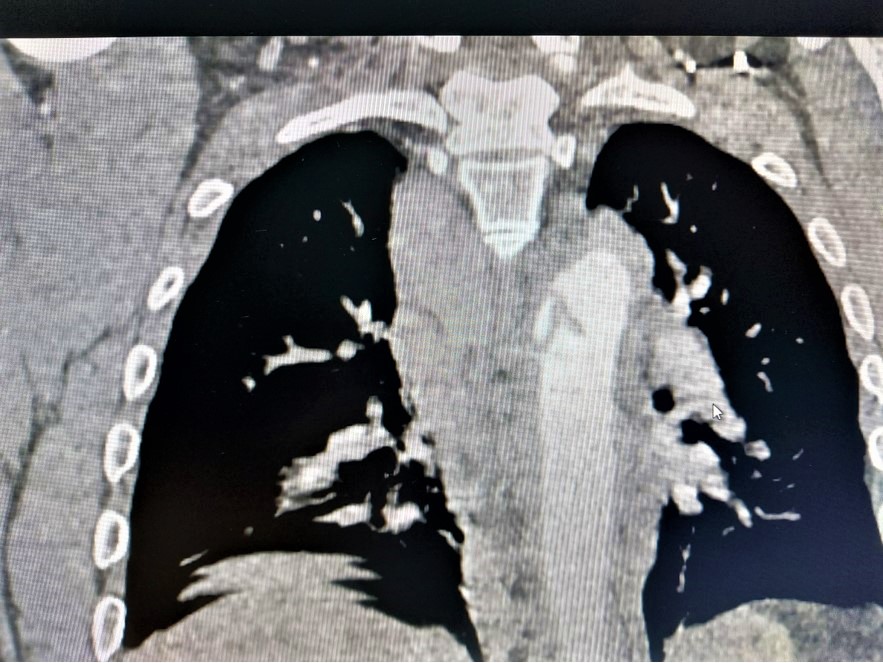

На пациентот му било дијагностицирано раскинување на ѕидот на градната аорта, по сообраќајна незгода со повеќе скршеници на коски и повреда на белите дробови. Ова претставува животно загрозувачка повреда која носи ризик од масивно крварење, без можност за прекин, поради што смртноста е скоро 100%.

Во ангио-сала на клиниката, кај пациентот, во целосна анестезија, беше направена хируршка препарација на артерија на ногата, со што се отвора место во артеријата за да се внесе посебен вид на стент обложен со материјал. Стентот со дијаметар 30 мм и должина 200 мм, беше поставен веднаш после артерија субклавија, односно артеријата која носи крв во левата рака и главата. Сложеноста на оваа процедура е позиционирањето на стентот. Тој треба да го покрие раскинувањето на ѕидот на аортата, кое беше на самиот отвор на артеријата за раката, но притоа стентот да не го прекине протокот на крвта за раката и главата.

Процедурата помина уредно, со целосно покривање на оштетувањето на аортата и со зачуван проток кон раката и главата. Артеријата на ногата хируршки беше “сошиена”, а пациентот успешно разбуден после анестезијата.